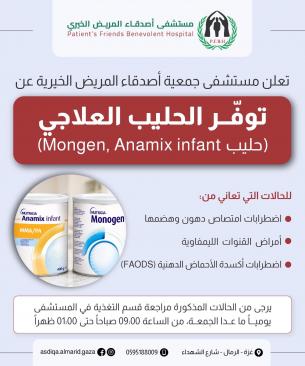

كيف تأكل المرضعة لتزيد حليبها وتخفّض من وزنها ؟